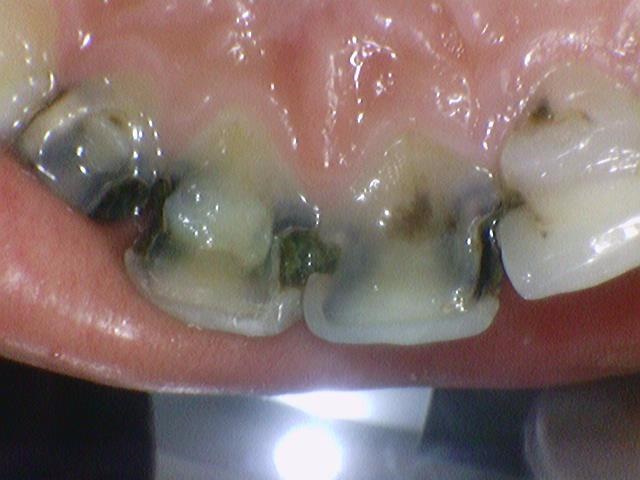

충치를 제거했더니 남는 치아부분이 이렇게 밖에 없는 상태ㅠㅠ

20대 환자분인데도 어떻게 이런 앞니로 학교다니고 사회생활 하셨냐며...

대문이 2개는 신경치료하고 앞니 크라운 2개 하셔서 2개는 크라운까지 완성된 상태구요.

사진상 오른쪽(환자분 기준으로는 왼쪽) 두번째 치아는 아직 크라운을 못하시고

신경치료 하고 사회생활은 하셔야하니 현재 레진으로 만들어놓은 임시 상태인데